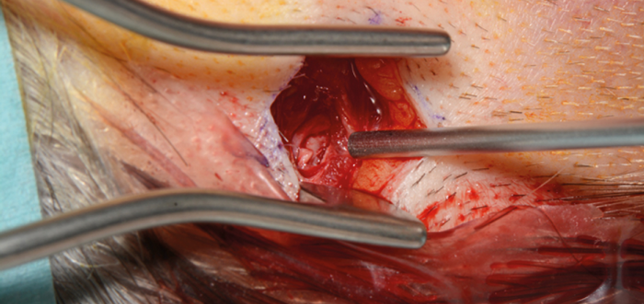

Parathyroidectomy